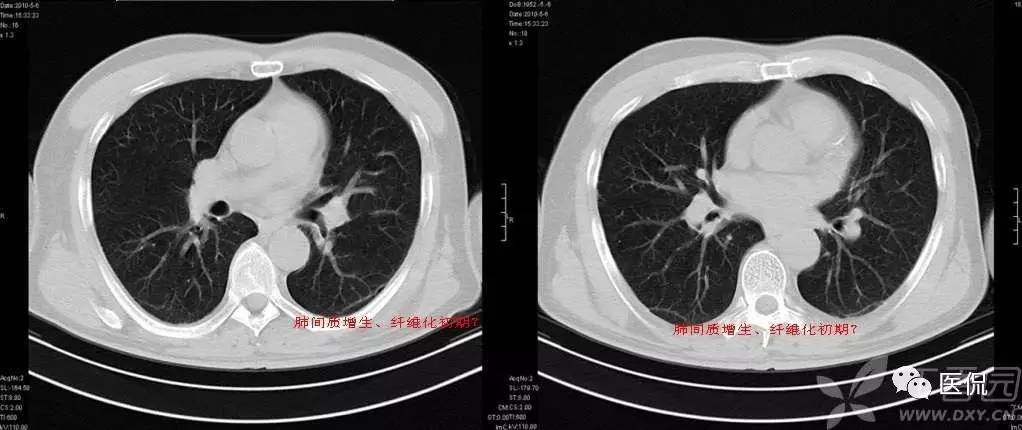

碎石路征

碎石路征或称铺路石征,是胸部CT上的一种影像学征象,主要表现为在弥漫性或散在分布的毛玻璃样浸润影中,有小叶间隔增厚、小叶内线状影重叠存在。碎石路征最初在肺泡蛋白沉积症(PAP)的病例中发现,并认为是PAP特征性的胸部CT表现;但实际上,感染性疾病、肿瘤、特发性肺弥漫性疾病(DPLD)、吸人性病变等都也可以出现。

1)PAP是一种罕见病。各个年龄均可发病,以20~50岁的成年人多见。干咳、呼吸困难是其最常见的临床症状,而胸膜性胸痛、乏力、低热等则较少见。其胸部X光片表现是双侧对称性的肺泡实变或毛玻璃影,主要分布于肺门及肺门周围而类似肺水肿。CT的典型表现包括:①毛玻璃影及实变影与小叶间隔增厚交织形成碎石路征样改变;②在肺泡实变与正常的肺实质之间出现很明显的分界线,形成“地图样”分布。PAP碎石路征的组织学基础是:毛玻璃影及实变影与肺泡内充满PAS染色阳性、富含脂质的蛋白样物质有关;小叶间隔增厚影与肺泡壁因纤维组织增生或II型肺泡上皮细胞增生及淋巴细胞浸润有关。依据碎石路征和“地图样”分布,结合患者临床与影像学表现不平行的特点,是诊断PAP的诊断的不要依据。